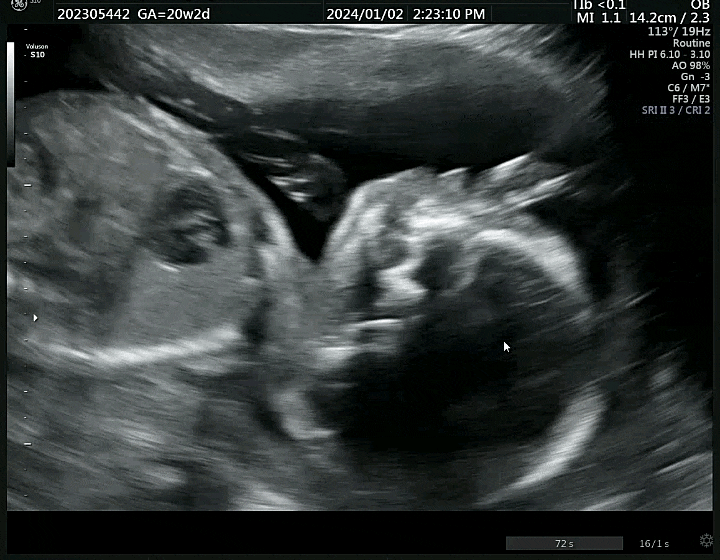

[임신 20주차] 정기검진 (임신성 물혹, 성별확인 등), 증상(손마디 저림, 임산부 잇몸부음 해결)

안녕하세요 벌써 임신 반환점에 와 있는 한방이 맘이에요! 어느새 청룡띠 아가 맘들의 출산의 해가 밝았어...

[임신 22주차~24주차] 정밀초음파검사, 임산부 주차별 증상(팔손저림, 쥐젖, 식욕)

22주차 정밀초음파를 진행했어요! 3주 만에 보는 한방이 정밀초음파는 약 30분가량 진행되었는데 정밀 초음...